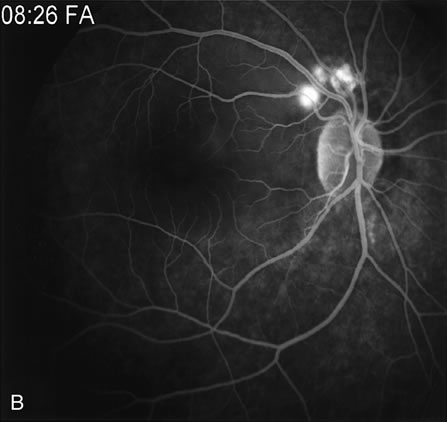

FA is also useful in characterizing two other subgroups of CNV: retinal angiomatous proliferation (RAP)8–16 and polypoidal choroidal vasculopathy (PCV).17–50 RAP begins in the deep retinal complex, forming intraretinal neovascularization (IRN), which may subsequently progress to extend beneath the neurosensory retina, forming subretinal neovascularization (SRN), and a vascularized PED.8 In the later phases of the process there may be a retinal-choroidal anastomosis (RCA). Clinical features of RAP include intraretinal hemorrhages, cystoid macular edema, and associated vascularized PED. FA is useful in revealing the presence of the angiomatous intraretinal vascular complex and the extension of the associated PED (Figs. 12 and 13). However, other diagnostic techniques such as indocyanine green (ICG) angiography, and optical coherence tomography (OCT) may be able to better demonstrate the presence of the RAP lesion.

Fig. 12. A. Clinical photograph of a retinal angiomatous proliferation (RAP) lesion (arrow). Note the intraretinal angiomatous proliferation, a feeding retinal arteriole, and a draining retinal venule, as well as the presence of intraretinal hemorrhages. B–C. Fluorescein angiography reveals late leakage from the RAP lesion.